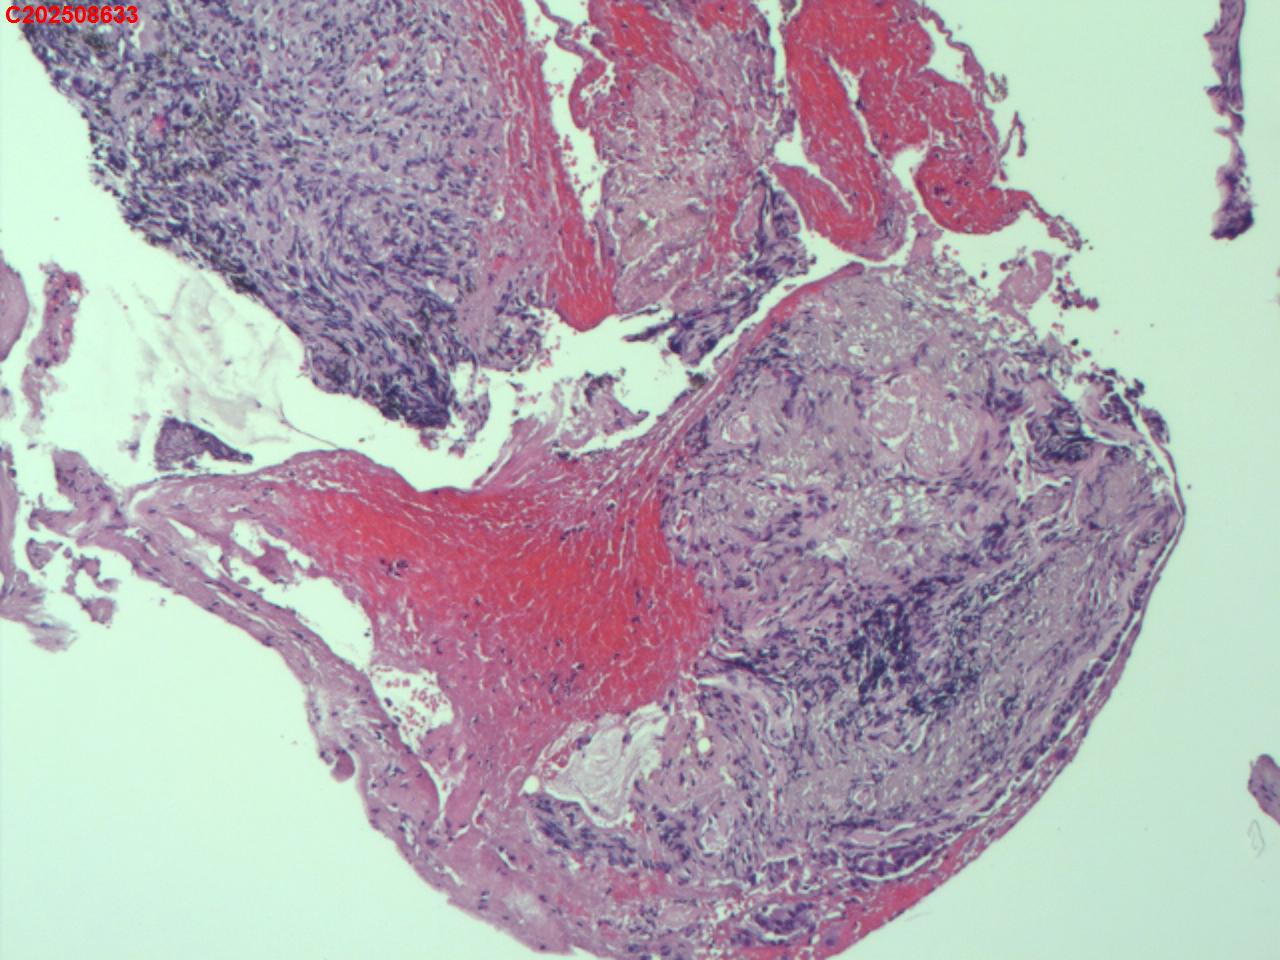

性别年龄82岁临床诊断肺结核?肿瘤?肺部感染?

一般病史2025-07-24 CT检查:考虑右肺上叶炎症伴肺实变,右肺上叶前段支气管显示不明确,建议治疗后复查或支气管镜检查。纵膈多发淋巴结增大。右侧胸腔积液。

标本名称纤支镜咬检

大体所见2025-07-25 气管镜检查示:左侧主支气管、上叶、下叶及各段支气管未见异常。右侧主支气管未见异常。右侧中间段支气管可见碳沫沉积。右肺上叶前段支气管开口可见脓苔附着,支气管开口狭窄,内可见灰黑色新生物阻塞右肺上叶前段支气管管腔。2025-07-25结核感染T细胞检测阳性。2025-07-27肺泡灌洗液查结核分枝杆菌复合群阳性。

坏死物比较多,没有看到明确的肿瘤性病变,可以考虑给一个描述性诊断。